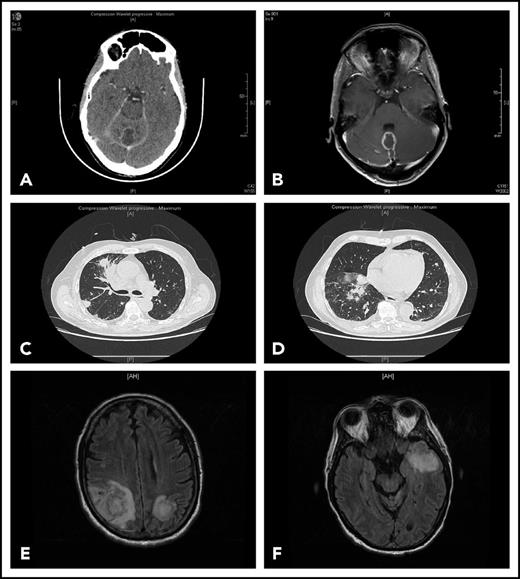

Representative findings in 2 patients with IFI. Patient 1 had been receiving ibrutinib 420 mg/d for 4 months for CLL associated with grade 3 autoimmune neutropenia when she complained of gait disorder. Computed tomography scan (A) and T1-weighted magnetic resonance imaging with gadolinium injection (B) revealed a solitary abscess of the vermis. Neurosurgical drainage disclosed Aspergillus fumigatus. Patient 2 was hospitalized after a third cycle of bendamustine, rituximab, ibrutinib for fever, cough, and confusion. Chest computed tomography scan revealed multiple pulmonary nodules (C-D) and T2-weighted fluid attenuation inversion recovery (FLAIR) magnetic resonance imaging multiple cerebral abscesses (E-F). Aspergillus antigenemia was strongly positive, and Aspergillus fumigatus was isolated in the bronchoalveolar lavage.